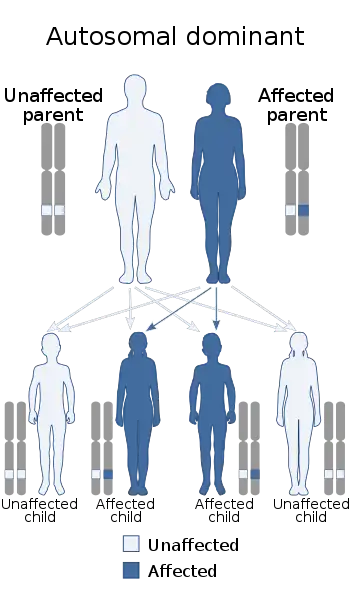

| This condition is inherited in an autosomal dominant manner | |

Families are defined as having HP,[5] if the phenotype is consistent with highly penetrant autosomal dominant inheritance. In simple terms, this would require two or more first degree relatives (or three or more second degree relatives) to have unexplained recurrent-acute or chronic pancreatitis in two or more generations. It is an autosomal dominant disease with penetrance that is generally accepted to be ≈80%.[1][20]